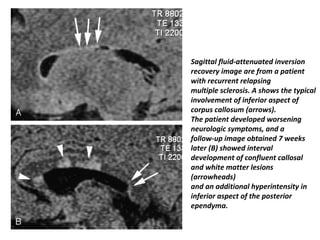

Sagittal fluid-attenuated inversion

recovery image are from a patient

with recurrent relapsing

multiple sclerosis. A shows the typical

involvement of inferior aspect of

corpus callosum (arrows).

The patient developed worsening

neurologic symptoms, and a

follow-up image obtained 7 weeks

later (B) showed interval

development of confluent callosal

and white matter lesions

(arrowheads)

and an additional hyperintensity in

inferior aspect of the posterior

ependyma.

Sagittal fluid-attenuated inversion recoveryimage are from a patient with recurrent relapsing multiple sclerosis. A shows the typical involvement of inferior aspect of corpus callosum (arrows). The patient developed worsening neurologic symptoms, and a follow-up image obtained 7 weeks later (B) showed interval development of confluent callosal and white matter lesions (arrowheads) and an additional hyperintensity in inferior aspect of the posterior ependyma.